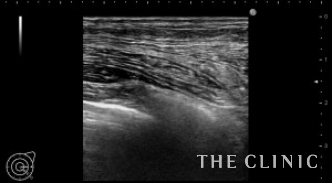

左)吸引後の状態です。カプセルは残っていますが、壊死脂肪はほとんど消失しました。右)除去した壊死脂肪です。

これだけ大きなしこりはカプセル内に液体が貯留する場合がありますが、フォローアップのエコーでは問題ありませんでした。